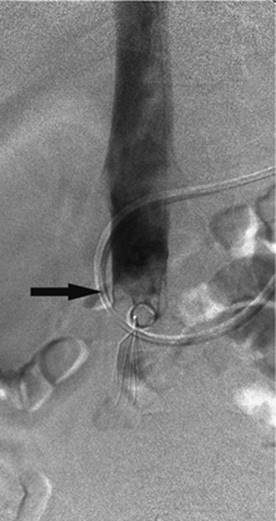

000452

Figure 35.22. Attempted canalization of the portal vein during a transjugular intrahepatic, portacaval shunting (TIPS) procedure. This CO2 injection identifies canalization of the hepatic artery (black arrow).

Puncturing the portal vein has proved to be difficult in some cases. Thrusting a large needle blindly through the liver parenchyma can cause a host of complications including bleeding from the liver capsule if the needle perforates the capsule of the liver. Hemobilia can be seen if the needle perforates a bile duct in close proximity to a vascular structure. The needle may leave the capsule of the liver and puncture adjacent organs including the intestine, gallbladder, kidney, and aorta, among others (Figs. 35.22–35.24).

000454

Figure 35.23. Attempted canalization of the portal vein during a transjugular intrahepatic, portacaval shunting (TIPS) procedure. The tip of the cannula is in the renal pelvis (black arrow).

Shunt malfunction can also be considered a complication. Acute thrombosis has already been discussed, but delayed thrombosis is also noted, as well as restenosis and stent shortening. Stenoses within the TIPS may form anywhere along the shunt from the portal vein to the IVC. Stenosis near the end of the stent is usually caused by a stent that is too short and leaves an area of the liver exposed. This leads to narrowing and, ultimately, stent occlusion. Restenosis within the stent itself has been seen, particularly with uncovered stents, and is thought to be related to bile being exposed to the shunt and the development of intimal hyperplasia; this has largely been resolved by the use of covered stents. Finally, the postprocedure right atrial pressures are going to be higher than preprocedure values. If the absolute value is greater than 10 mm Hg, diuresis is recommended.

000459

Figure 35.24. Attempted canalization of the portal vein during a transjugular intrahepatic, portacaval shunting (TIPS) procedure. The tip of the cannula is in the left hepatic duct (black arrow). Contrast is noted throughout the biliary system and into the common bile duct (white arrow).